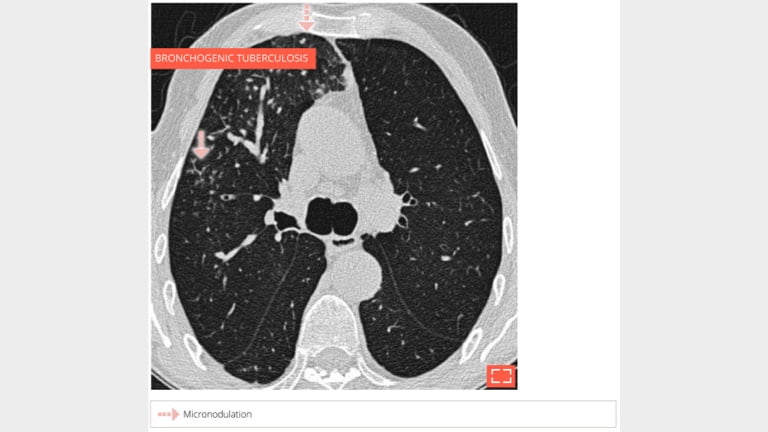

Centrilobular and perilymphatic micronodulation.

Micronodulation in the ventral segment of the right upper lobe sparing the subpleural part of the lung.